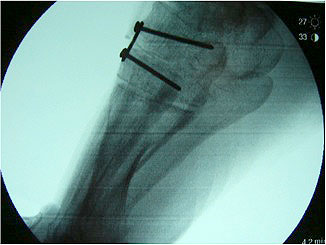

Radiologisches Beispiel einer fixierten Planovalgus Deformität Stadium III, 51 jähriger Patient. Stehendes präoperatives Röntgenbild und 1 Jahr postoperatives Röntgenbild des Fußes seitlich. Die Korrektur der Deformität umfaßte eine leicht korrigierende U

Abbildung 12

Im Stadium III der Tibialis posterior Sehneninsuffizienz bei fixierter Deformität und/oder erheblich eingeschränkter Inversion im USG aber stabilen und flexiblen Chopart-Gelenk und weniger als 10° fixierter Vorfußsupination eine in-situ oder leicht korrigierende USG-Arthrodese indiziert. Der Vorteil einer isolierten USG-Arthrodese gegenüber einer Triple- oder Double-Arthrodese ist die verbleibende, funktionell wichtige Beweglichkeit in der Chopart-Gelenkreihe. Um einem persistierenden fibulocalcanearem Impingement sicher vorzubeugen, sollte die USG-Arthrodese in maximal 5° Valgus- oder sogar Neutralposition erfolgen. Zur Prophylaxe eines Rezidivs wird die USG-Arthrodese zudem häufig mit einer medialisierende Tuber calcanei Osteotomie und / oder einem FDL-Transfer kombiniert (Abb. 12).